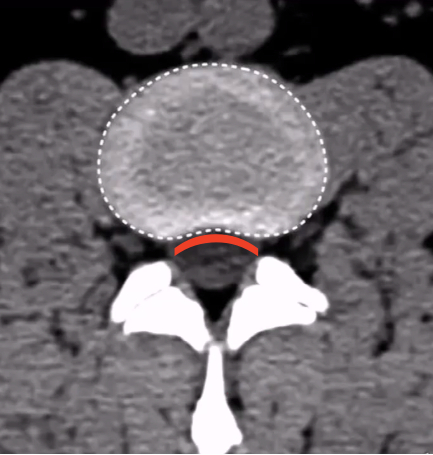

广医三院脊柱外科副主任医师王簕为小阳做了详细的检查,经CT、MRI检查后发现,小阳的腰5/骶1椎间盘膨出并偏右后方突出,右侧侧隐窝变窄,右侧神经根受压。